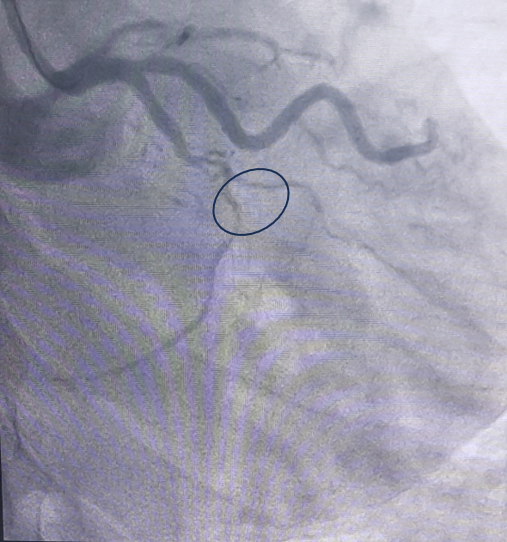

Người bệnh được chỉ định chụp động mạch vành qua hệ thống máy chụp mạch máu số hoá xoá nền (DSA), kết quả cho thấy tắc hoàn toàn cả 3 nhánh động mạch vành, đặc biệt các mạch tắc được nuôi dưỡng bằng mạch tuần hoàn bàng hệ từ chính những nhánh tắc.

| Tắc hoàn toàn động mạch vành phải) Tắc hoàn toàn động mạch mũ bên trái |

Đây là trường hợp tổn thương mạch vành nặng, phức tạp và khá hiếm gặp. Người bệnh có tổn thương động mạch vành tiến triển từ từ và kéo dài từ trước, các mạch máu tuần hoàn phụ phát triển nhanh đủ để ngăn cản sự thiếu máu cơ tim nên trước đó người bệnh không có dấu hiệu bất thường. Bệnh chỉ được phát hiện khi các mạch máu phụ phát triển không đủ lớn để duy trì lưu lượng máu đáp ứng nhu cầu oxy của cơ tim gây thiếu máu mạch vành, gây nhồi máu cơ tim cấp.